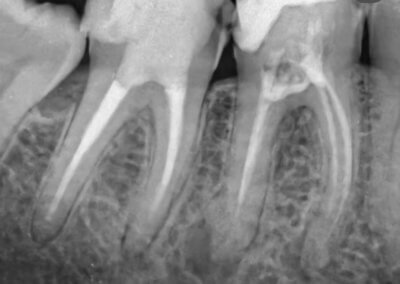

Endodonția este o ramură esențială a stomatologiei, axată pe diagnosticarea, prevenirea și tratamentul afecțiunilor pulpei dentare și a țesuturilor periapicale. Această specialitate joacă un rol crucial în salvarea dinților naturali, evitând extracțiile și menținând sănătatea orală pe termen lung. Prin tehnici avansate și echipamente de ultimă generație, endodonția asigură tratamente precise și eficiente, contribuind la redarea sănătății și funcționalității dinților într-un mod durabil și predictibil.

Reconstituirea coronară cu materiale de calitate conferă rezistență pe termen lung.

Tratamentele corecte reduc riscul de infecții și complicații viitoare.